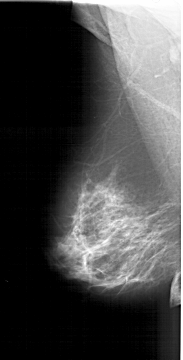

A_1382_1.RIGHT_MLO

A_1382_1.RIGHT_CC

RIGHT_CC LINES 5731 PIXELS_PER_LINE 2836 BITS_PER_PIXEL 12 RESOLUTION 43.5 OVERLAY

RIGHT_MLO LINES 5866 PIXELS_PER_LINE 2911 BITS_PER_PIXEL 12 RESOLUTION 43.5 OVERLAY

FILE: A_1382_1.RIGHT_MLO.OVERLAY

TOTAL_ABNORMALITIES 1

ABNORMALITY 1

LESION_TYPE CALCIFICATION TYPE PLEOMORPHIC DISTRIBUTION CLUSTERED

ASSESSMENT 4

SUBTLETY 3

PATHOLOGY BENIGN

FILE: A_1382_1.RIGHT_CC.OVERLAY